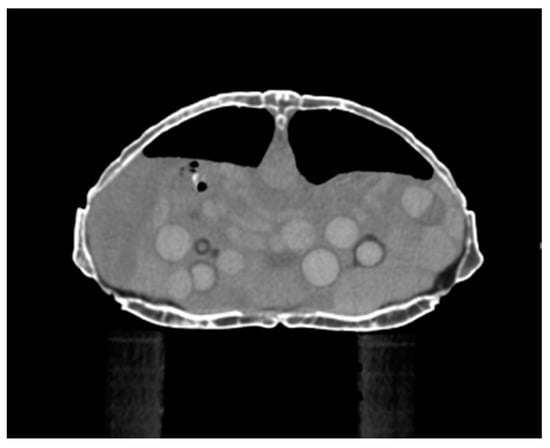

2.2.3. Computed Tomography

5.1. Preovulatory Follicular Stasis (PFS)

5.1.3. Diagnosis